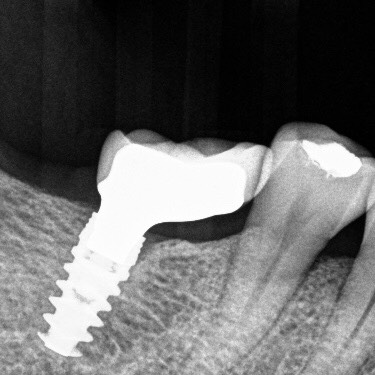

The bone surrounding a dental implant is the foundation for it’s long-term success – just like the solid foundation of your beautiful home. Without good quality and quantity of bone, it is hard to achieve a predictable outcome during surgery. With bone grafting, we have an opportunity to promote new bone growth and replace bone where it is missing.

Before an implant is placed, it is critical to have the placement of your missing tooth pre-planned before surgery. If there is not enough bone, there are two options.

Not all dental implants are made equal. Predictable success comes from quantity and quality of bone, your immune system, and surgical skill. If we have a strong foundation for the implant and abundance of good bone, we will have greater success. Grafting is important in implant dentistry.